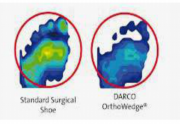

| 08:06, 23 במאי 2013 | מיפוילחצים1.png (קובץ) |  |